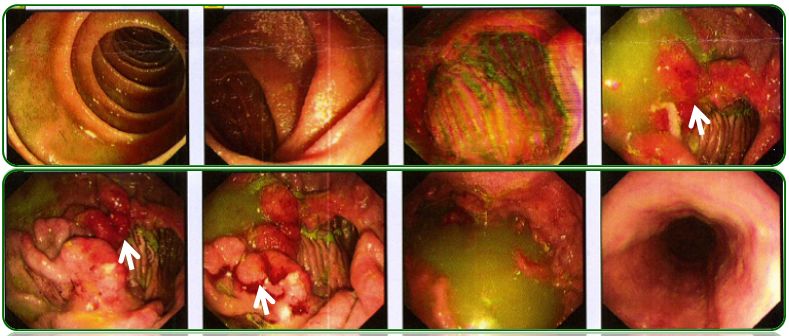

胃镜、肠镜未见异常,如图6;

肺部CT提示双肺纹理增多、左侧胸腔少量积液,如图7a-b;

腹部彩超示腹腔积液,如图7c。

图6 胃镜、肠镜检查

图7 胸部CT及腹部彩超检查

回归本例患者在门诊给予促进胃肠动力及补充消化酶治疗效果欠佳,因此行腹部彩超检查,提示腹腔积液,门诊收住院进一步检查。由于患者上腹部胀痛,进食后明显,查体剑突下轻压痛,毫无疑问胃镜检查必须做,腹腔积液患者也需要排除肠道肿瘤,因此肠镜也需要完善,所幸的是胃肠镜检查均未发现异常。

常规胸片检查提示胸腔积液,因此进一步行肺部CT检查,提示肺部CT提示双肺纹理增多、左侧胸腔少量积液,似乎本例和例2非常相似,同时胸腹腔积液。完善了腹部彩超、肝炎病毒学和PPD试验等检查,初步排除了肝硬化和结核菌感染,也未发现肿瘤征象。那么到底是什么原因呢?